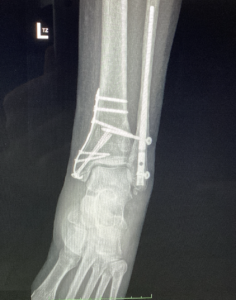

Operácia bola vykonaná 19. septembra 2025, počas ktorej bola realizovaná osteosyntéza klincom Vitus a mediálnou dlahou Arthrex, aby sa zabezpečila stabilita kostí a ich správne hojenie. Po zákroku bola končatina imobilizovaná v termoplastickej dlahe, čo je bežný postup v období bezprostredne po operácii, ktorý umožňuje ochranu operovanej oblasti a zároveň podporuje správne zhojenie kostných štruktúr.

Pri kontrole sa ukázalo, že rozsah pohybu mechanicky obmedzuje jedna zo stabilizačných skrutiek. Preto bola 21. januára vykonaná menšia operačná revízia, počas ktorej došlo k odstráneniu skrutky, ktorá bránila ďalšiemu zlepšeniu mobility členka.